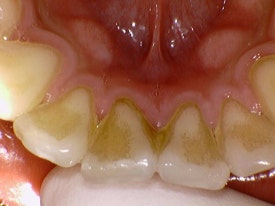

위 사진은 본원에서 진행한 스케일링 전 후 사진입니다.

보기만 해도 너무너무 시원하죠!